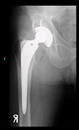

The guiding wire was inserted and controlled with fluoroscopy flashes (Figure 4). The drilling and reaming were carried out in accordance with the recommendations:

Figure 4.

The biocompatible aiming device after insertion of the guiding wire.

The radiological examination allowed us to verify the close bone-to-implant contact and the unchanged position of the implant during follow-up.

In all the cases operated with the above-described targeting procedure, the stems of the cups remained between the cortical bone surfaces without perforation of the linea terminalis, as shown by postoperative radiographs. There were no complicated surgical situations. In 16 cases, the wound healings were uneventful, and the hips were able to bear weight again after postoperative rehabilitation.